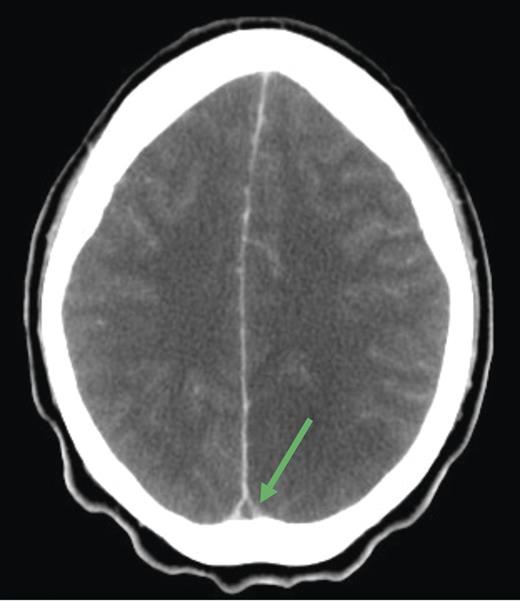

Cranial computed tomography (CT) demonstrated subtle hypodensity mainly in the left occipital lobe, with a characteristic empty delta sign (Fig. 1). Computed tomography angiography demonstrated normal filling of the posterior cerebral arteries (PCA). Cranial magnetic resonance imaging (MRI) evaluations demonstrated bilateral ischemic changes involving the occipital and parietal lobes, more extensively on the left (Fig. 2). Magnetic resonance venography (MRV) demonstrated complete occlusion of the left transverse and sigmoid sinuses, as well as near occlusion of the posterior superior sagittal sinus (Fig. 3C).

Diagnosis of CVT is substantiated with neuroimaging. An abnormal sinus signal coupled with an absence of flow on MRV strengthens the diagnosis. If diagnosis is still uncertain at this stage, cerebral angiography may be attempted as it provides definitive information of the cerebral arterial and venous system. An empty delta sign is the most commonly observed sign of CVT on CT imaging (such as our patient), but this is only present in 20% of cases.